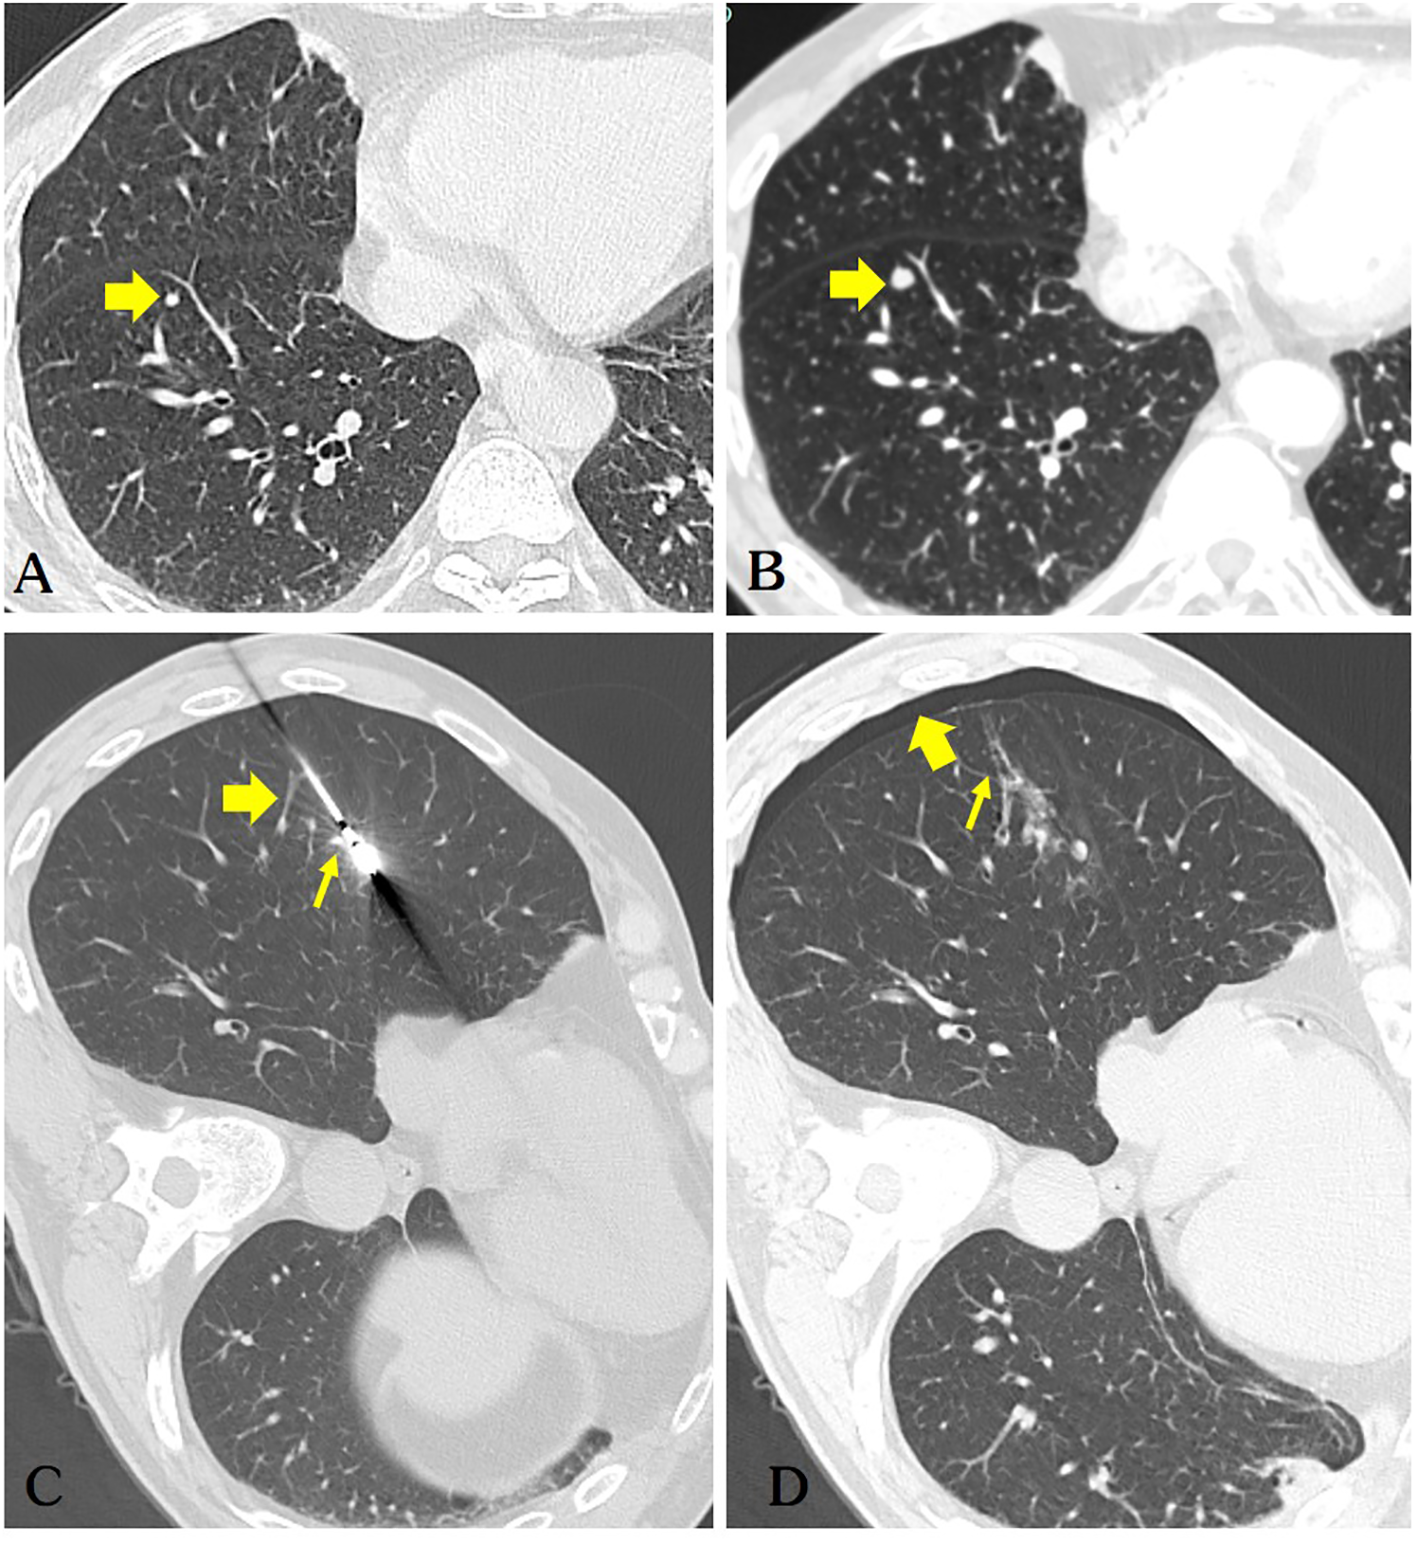

Figure 1

(A) The patient’s chest CT scan shows a solid nodule (diameter of 3.1mm) in the right lower lobe of the lung(arrow). (B) A repeat chest CT scan after 5 months indicates a significant increase in the size of the nodule (diameter of 5.2mm) in the right lower lobe, highly suspicious for pulmonary metastasis (arrow). (C) The microwave antenna accurately punctured the lesion. Retrospective analysis considered puncture of the pulmonary vein(thick arrow) and pulmonary artery(thin arrow). (D) The patient developed a small right-sided pneumothorax post-operatively (thick arrow), while air was observed in the ablation needle tract (thin arrow), which is a very dangerous sign.